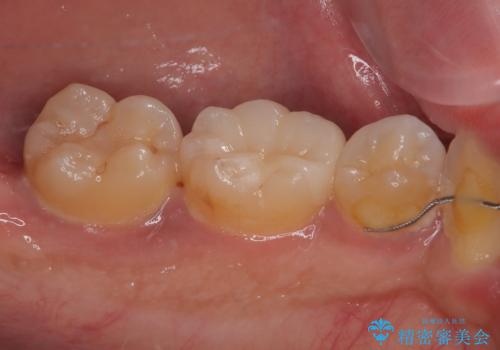

セラミックインレーの装着時には、唾液の侵入を防ぐために、ラバーダム防湿を行いました。

見た目、機能面共に大変喜んでいただきました。